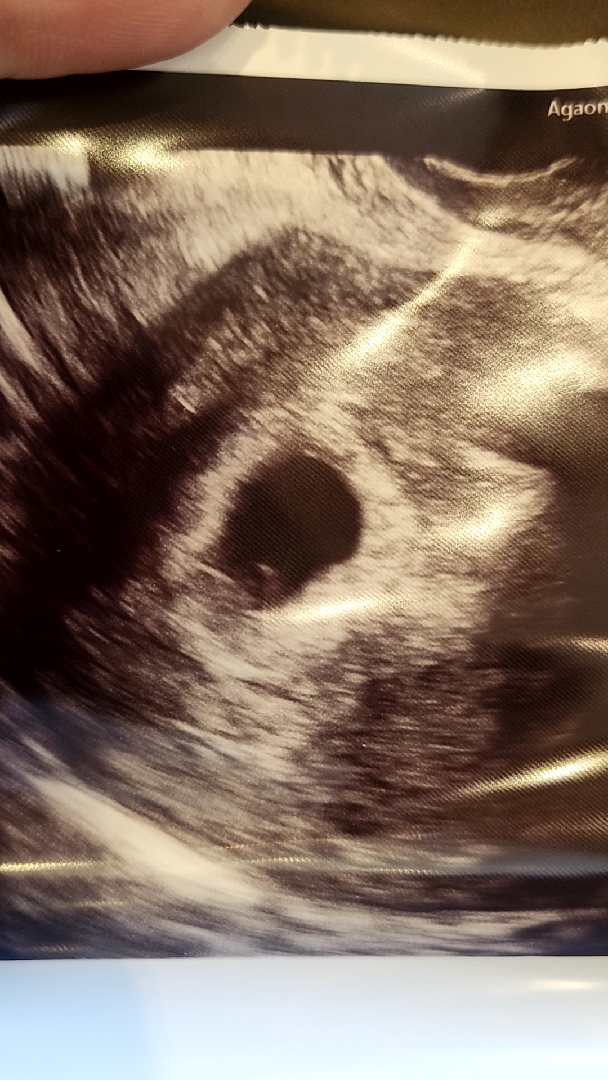

6주0일난황보고왔어요

오늘병원가서 촘파로 난황보고 왔는데요 아기도 볼수있을줄 알았는데 아직 또렸하지가 않다고 하시는데 사진 한번 봐주실수 있으세요?ㅠㅠ 선생님은 몇일있다가 잘보일꺼라고 하셨는데..걱정되서요

저도 오늘 난황까진 보이는데 아기가 안보였어요 ㅜㅜ

며칠 있다가 동그랗게 잘 보일거 같은데요?!